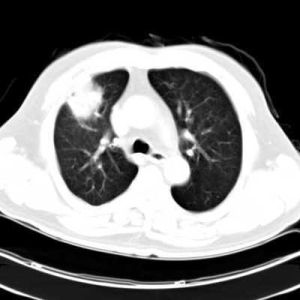

6.CT掃描見形狀不規則、邊界不圓滑、不均質軟組織塊影或占據眶內一部分或全眶區的雲霧狀高密度影。